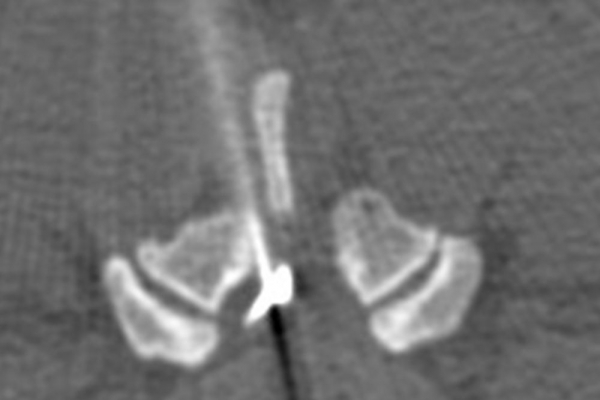

Με την βοήθεια της επεμβατικής ακτινολογίας είναι δυνατόν να πραγματοποιηθούν διαφορες ενέσιμες τεχνικές που αποσκοπούν στη μείωση του μυοσκελετικού πόνου, την ενίσχυση της αποτελεσματικότητας της φυσιοθεραπείας και την επιτάχυνση της διαδικασίας επούλωσης. Οι τεχνικές αυτές περιλαμβάνουν την κατευθυνόμενη έγχυση φαρμάκων ή πραγματοποίηση θεραπευτικών χειρισμών ακριβώς στη θέση τηςπαθολογία. Ετσι εξασφαλιζεται η μέγιστη αποτελεσματικότητα ( έως 95% κατά περίπτωση) και ασφάλεια σε σχέση με τυφλούς χειρισμούς χωρίς ακτινολογική καθοδήγηση.